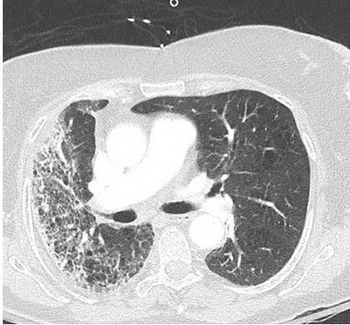

Results of a physical examination and CT scan of the chest offer clues to this patient's diagnosis.